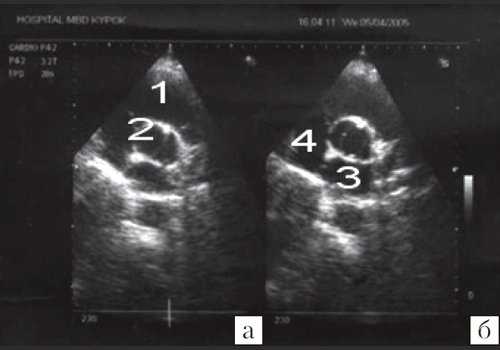

![Эхокардиограмма больного С (парастернальная позиция по короткой оси на уровне митрального клапана)]()

Рис. 5. Эхокардиограмма больного С. (парастернальная позиция по короткой оси на уровне митрального клапана).

1 - правый желудочек; 2 - левый желудочек; 3 - аневризма межжелудочковой перегородки; 4 - митральный клапан с двойным отверстием.